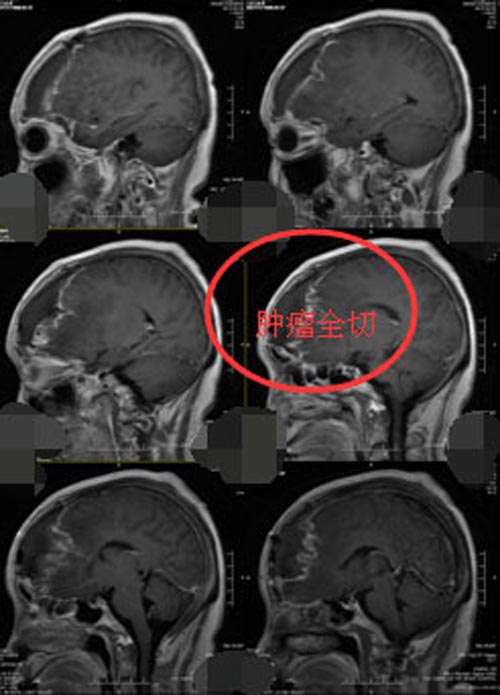

排除手术禁忌症后,神经外五科手术团队在全麻下行“左侧额部大脑镰窦旁脑膜瘤切除+左侧大脑中动脉动脉瘤夹闭术”,术中导航定位,切开额部硬脑膜后,局部脑组织肿胀严重,可见暗红色肿瘤, 分块切除后,可见坏死组织血供丰富,与大脑镰和矢状窦密切相连,仔细分离全切后,又取左侧翼点入路,充分暴露大脑中动脉M1M2段上下干后,可见上干有一3mm×2mm的囊状动脉瘤,小心夹闭后予术中TCD检测,吲哚菁绿造影展示大脑中动脉M1和M2段上下干保留完好,麻醉满意,手术顺利。术后病理检验结果示:左额脑膜皮细胞型脑膜瘤,WHO I 级,本例细胞增生活跃。术后头颅CT示:左额脑膜瘤切除术后+左侧大脑中动脉瘤夹闭术后。

▲手术后